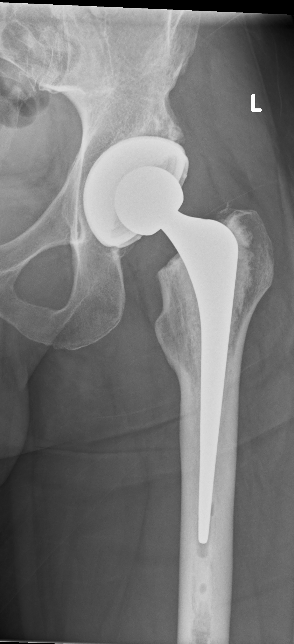

Ms Chloe Scott is a Consultant Trauma and Orthopaedic Surgeon with a specialist interest in hip and knee arthroplasty and lower limb trauma. She has a particular expertise in partial knee replacement surgery, robotic assisted joint replacements and in complex knee replacement surgery including revision.

Ms Scott graduated from the University of Edinburgh medical school in 2004. She completed her orthopaedic training in Edinburgh during which time she also completed higher degrees in Orthopaedic Engineering at Cardiff University and in partial knee replacement design at the University of Edinburgh. She completed travelling fellowships in Boston, Chicago, and South Carolina USA.